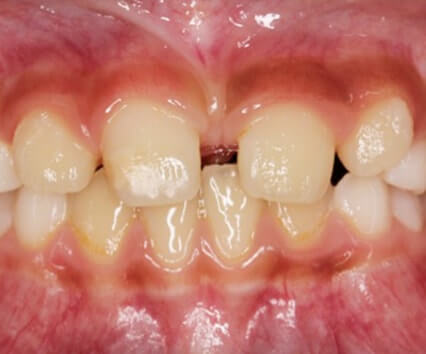

萌出異常(乳歯の裏から歯が生えてきた)